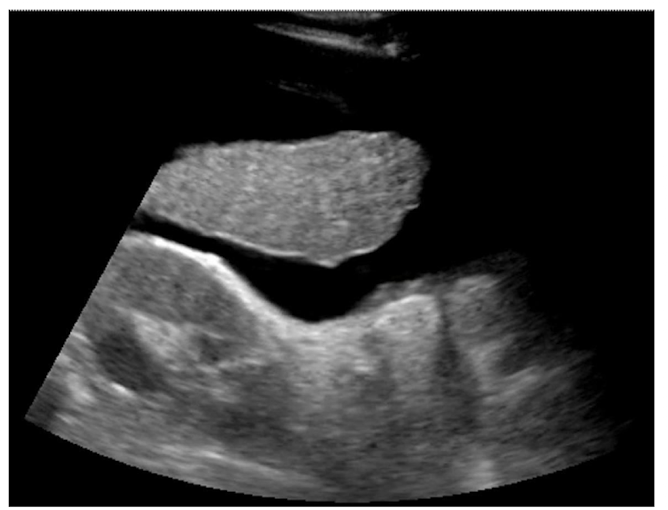

True or false: Exudative ascites is shown in this image

False; the fluid is anechoic, transudative ascites